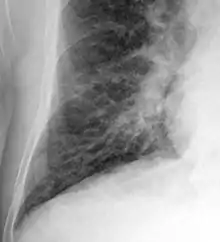

Chest X-ray

Chest X-rays are frequently used to aid in the diagnosis of CHF. In a person who is compensated, this may show cardiomegaly (visible enlargement of the heart), quantified as the cardiothoracic ratio (proportion of the heart size to the chest). In left ventricular failure, evidence may exist of vascular redistribution (upper lobe blood diversion or cephalization), Kerley lines, cuffing of the areas around the bronchi, and interstitial edema. Ultrasound of the lung may also be able to detect Kerley lines.[73]

Congestive heart failure with small bilateral effusions

Kerley B lines